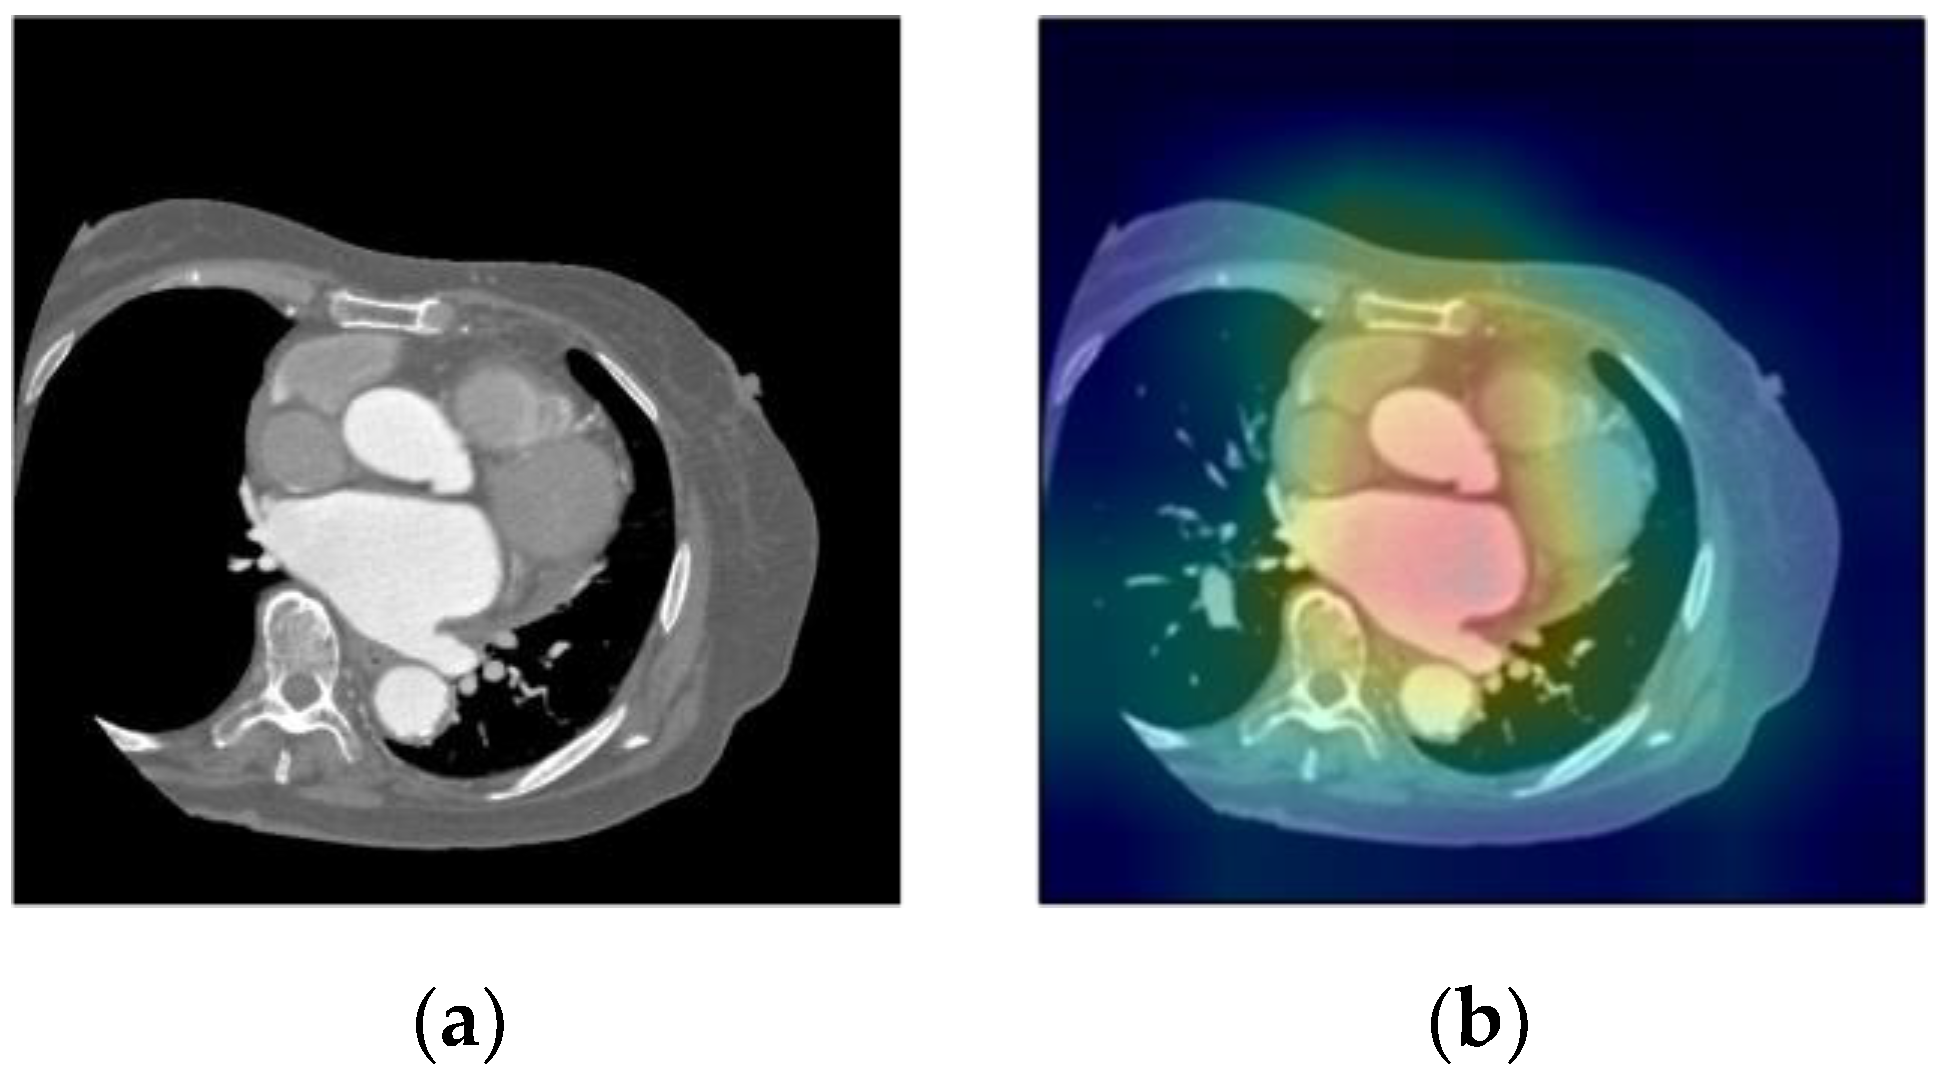

In this study, we used score-class activation mapping (CAM) to visualize the points of interest by highlighting the pixels that contributed to the classification results according to their importance. Score-CAM eliminates the dependence on gradients by obtaining the weight of each activation map through its forward passing score on the target class; the final result is obtained using a linear combination of weights and activation maps [23]. It visualizes the importance based on the results obtained by providing the generated images to the CNN using the feature map obtained when the trained CNN infers a specific image. The resulting feature map was enlarged to the size of the input, normalized to a value between 0 and 1, and multiplied by the input image to generate a heatmap. The output of CAM is shown as a heatmap overlaid on the image. This heatmap is called a saliency map in CAM. The input and saliency map images are shown in Figure 3.

Figure 3.

An example of visualization of decision basis in CNN (score-CAM). (a) Input image; (b) saliency map image.